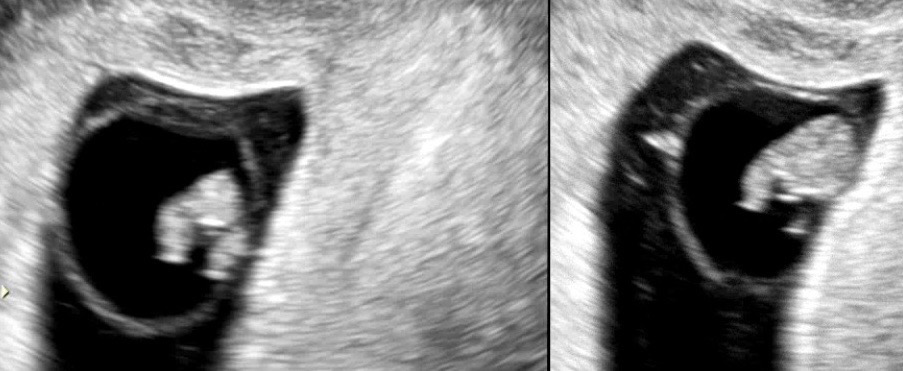

(8w5d) 통닭다리 구경하세요

통닭다리 너무 귀여워서 팔불출 짓인거 알면서도 올려봅니다. 옆에서 홉이맘이 적을때는 몇주며칠적어야한데서 8주5일입니다!